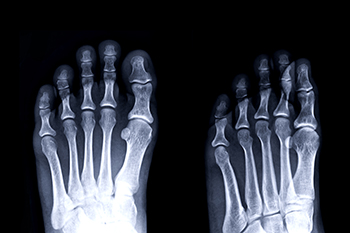

Due to the wide variety of potential causes of ankle pain, podiatrists will utilize a number of different methods to properly diagnose ankle pain. This can include asking for personal and family medical histories and of any recent injuries. Further diagnosis may include sensation tests, a physical examination, and potentially x-rays or other imaging tests.

Diagnosis

Treatment

Just as the range of causes varies widely, so do treatments. Some more common treatments are rest, ice packs, keeping pressure off the foot, orthotics and braces, medication for inflammation and pain, and surgery.